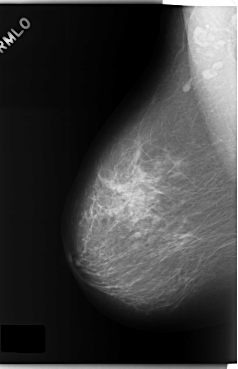

C_0173_1.RIGHT_MLO

RIGHT_MLO LINES 5896 PIXELS_PER_LINE 3808 BITS_PER_PIXEL 12 RESOLUTION 50 NON_OVERLAY